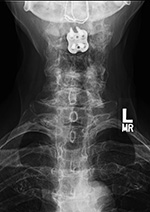

Posterior spinal wiring goes from C1 to C2. There is also solid posterior bony fusion mass from the occiput to C2 as well as an anterior cervical fusion plate and screws from C2 to C3 with interbody bony disk plug at C2-3. |